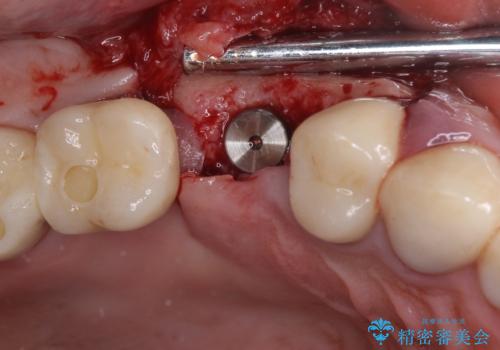

- 咬合力により歯が割れてしまった方のインプラント治療です。

抜歯後4ヶ月ほど待ち、後方のインプラントと同一メーカーのインプラントを埋入することとしました。

大変怖がりであるため、インプラント治療の際には静脈内鎮静により、眠っている間に手術を行いました。

別途費用はかかりますが、術中の記憶はほとんどなく、処置もあっという間に終わった感覚となるので、大変お勧めです。